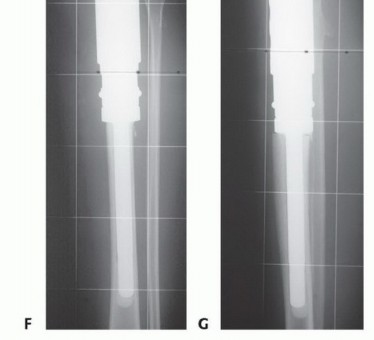

أورام قصبة الساق القريبة هي آفات عظمية معقدة تتطلب استئصالاً دقيقاً مع الحفاظ على الطرف. يشمل العلاج إزالة الجزء المصاب من قصبة الساق، ثم إعادة بناء مفصل الركبة باستخدام أطراف صناعية أو طعوم عظمية، مع التركيز على استعادة وظيفة الطرف وتقليل المضاعفات لضمان أفضل النتائج للمريض.

ومع ذلك، شهد العقدان الأخيران ثورة حقيقية في مجال جراحة أورام العظام، مدفوعة بالتقدم الهائل في تقنيات التصوير التشخيصي، والأساليب الجراحية الدقيقة، وتطور المواد المستخدمة في إعادة البناء. لم يعد البتر هو الخيار الوحيد، بل أصبح الحفاظ على الطرف (Limb Salvage) هو المعيار الذهبي للعلاج كلما أمكن ذلك، مما يمنح المرضى فرصة ثمينة للحفاظ على وظيفة أطرافهم، واستعادة حركتهم، وتحسين جودة حياتهم بشكل جذري.